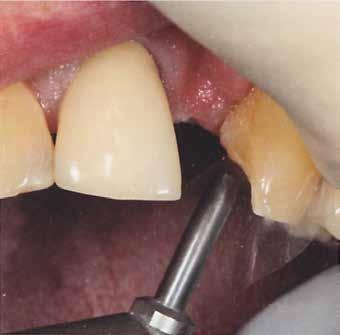

Ebben a cikkben egy olyan esetet ismertetünk, ahol a kezelés során alkalmazott munkafolyamatokat digitálisan végeztük el. Minimál-invazív preparációt követően – digitális mosolytervezés alapján – lithium-diszilikát tömbökből monolitikus héjakat és koronákat készítettünk CAD/CAM technológia felhasználásának segítségével. Az elkészült restaurátumok segítségével helyreállítottuk az elvesztett harapási magasságot, valamint megszüntettük az ebből adódó esztétikai hátrányokat és az emiatt kialakult temporomandibuláris ízületi diszfunkciót.

2015-ben egy 47 éves férfi páciens állkapocs-ízületi panaszai miatt kereste fel a rendelőnket. Ezen felül esztétikai problémát jelentett számára, hogy az egyik felső nagymetszőfogán lévő héj eltört (1-3. ábrák). A klinikai és radiológiai vizsgálatot követően megállapítható volt, hogy a páciens kifejezett bruxizmusa miatt csökkent a harapási magassága, és jelentős mennyiségű saját foganyagot abradált el (4. ábra)

Szájterpesz használata mellett digitálisan intraorális fotók készültek a páciensről mind frontális, mind laterális és okkluzális irányokból. További fotók is készültek a páciensről egy digitális tükörreflexes kamera segítségével (frontális és laterális irányból, valamint 45 o-os szögből). Mindkét állcsontról digitális lenyomat készült egy intraorális szkenner segítségével (Care stream 3500). A maximális-interkuszpidációs helyzetet (IKP) szintén a Carestream 3500-as készülék felhasználásával rögzítet -

A páciens a megkezdett kezelések folytatása miatt 2017ben ismét felkereste a rendelőnket (7. ábra). Ekkor egy új intraorális lenyomatvétel történt (Carestream 3600).

A fogak preparálásához egy új mock-upot készítettünk háromdimenziós nyomtató segítségével (SolFlex, VOCO) bisz-akrilátból (Structur 3). A mock-up elkészítéséhez felhasznált sablont vákuum technológia segítségével hoztuk létre (V-Print ortho, VOCO). A mock-up felhelyezését követően a páciens fogait minimál invazív módon készítettük elő (8. ábra).

A már előzetesen preparált felső frontfogak csiszolt csonkjainak megtartottuk az eredeti formáját. Az alsó és felső őrlőfogak preparációja nem volt szükséges (1.7-1.4, 2.4-2.7, 3.7-3.4, 4.4-4.7), az alsó kismetsző fogakat minimál invazív módon készítettük elő. Az előkészítést követően új digitális lenyomat készült. Az így kapott digitális adatokat továbbítottuk a fogtechnikai laboratóriumba (9. ábra). A virtuális modellt ezek alapján hozták létre (AnatomicLab), és a minta elkészítéséhez szükséges STL fájlt továbbították egy háromdimenziós nyomtatóra (SolFlex 650, VOCO), amely segítségével elkészítették az új mintát (V-Print model, VOCO).